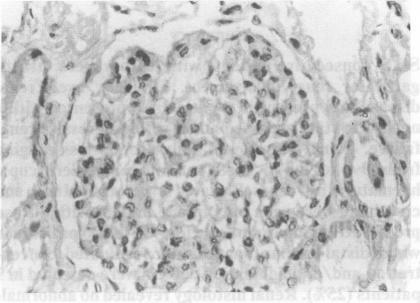

Sixty consecutive patients with leprosy were investigated for renal involvement. Clinically overt renal disease was present in 4 patients; 3 presented with a nephrotic state and one patient with progressive renal failure. Urinalysis showed daily protein loss ranging from 0.4 to 8.9 g in 8 patients and microscopic haematuria in 4 cases. Elevated levels of blood urea and creatinine were seen only in one patient with diffuse proliferative glomerulonephritis. Of the 36 patients in whom distal tubular functions were evaluated, concentration and/or acidification defects were detected in 9 patients (25%). Renal histology revealed no abnormality in any of these patients. Serum C3 levels were decreased in 5 patients with lepromatous leprosy and 3 patients with borderline leprosy. Histological evidence of renal involvement was detected in 9 patients (15%). Amyloid deposits were seen in 3 (5%) patients of whom 2 had lepromatous leprosy and one had tuberculoid leprosy with chronic trophic ulcers. Mesangial proliferative lesions were seen in 5 (8.3%) and diffuse proliferative lesions (with crescents in more than 70% of glomeruli) in one patient. All of them had lepromatous leprosy. Three of the 5 patients with mesangial proliferative glomerulonephritis had erythema nodosum leprosum at the time of biopsy. Immunofluorescence studies revealed granular deposits of IgA, IgM and C3 in one patient with mesangial proliferation and IgA/IgM with or without C3 in 3 more patients in whom renal histology was normal. Glomerulonephritis associated with leprosy appears to be immune mediated but confirmation requires identification of lepra antigen in the glomerular immune complex deposits.

对60例连续性麻风患者进行了肾脏受累情况调查。4例患者存在临床明显的肾脏疾病;3例表现为肾病状态,1例表现为进行性肾衰竭。尿液分析显示,8例患者每日蛋白质丢失量为0.4至8.9克,4例出现镜下血尿。仅1例弥漫性增殖性肾小球肾炎患者出现血尿素和肌酐水平升高。在评估了远端肾小管功能的36例患者中,9例(25%)检测到浓缩和/或酸化缺陷。这些患者的肾脏组织学检查均未发现异常。5例瘤型麻风患者和3例界线类麻风患者的血清C3水平降低。9例(15%)患者检测到肾脏受累的组织学证据。3例(5%)患者可见淀粉样沉积物,其中2例为瘤型麻风,1例为结核样麻风伴慢性营养性溃疡。5例(8.3%)可见系膜增殖性病变,1例可见弥漫性增殖性病变(超过70%的肾小球有新月体形成),所有患者均为瘤型麻风。5例系膜增殖性肾小球肾炎患者中有3例在活检时出现结节性红斑。免疫荧光研究显示,1例系膜增殖患者的肾小球中有IgA、IgM和C3的颗粒状沉积物,另外3例肾脏组织学正常的患者中有IgA/IgM伴或不伴C3。麻风相关的肾小球肾炎似乎是免疫介导的,但需要在肾小球免疫复合物沉积物中鉴定麻风抗原才能确诊。